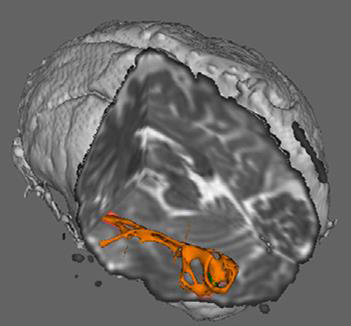

While many dyslexia studies focus on the cerebral cortex, the researchers, which included faculty from pediatrics, engineering, radiology, psychology, special education and other Vanderbilt departments and centers, targeted the sub-cortical thalamus region. The thalamus serves as the brain’s connector—relaying sensory and motor signals back to the cerebral cortex via nerve fibers that are part of the brain’s “white matter.” The thalamus also regulates alertness, consciousness and sleep.

Evaluating 40 children ages 8 to 17 years, evenly divided between typically developing readers and those with developmental dyslexia, the researchers used diffusion tensor imaging to visually map the structure of the brain in an effort to better understand the role of the thalamus in reading behavior.

“A different pattern of thalamic connectivity was found in the dyslexic group in the sensorimotor and lateral prefrontal cortices,” Cutting said. “These results suggest that the thalamus may play a key role in reading behavior by mediating the functions of task-specific cortical regions. Such findings lay the foundation for future studies to investigate further neurobiological anomalies in the development of thalamo-cortical connectivity in individuals with dyslexia.”

In a related study, the team examined connectivity patterns in a cortical region known to be especially important for reading: the left occipito-temporal region, sometimes referred to as the visual word form area.

Cutting and her colleagues used diffusion MRI to study the structural connectivity patterns in the left occipito-temporal region and surrounding areas of the brain in 55 children.

“Findings suggest that the architecture of the left occipito-temporal region connectivity is fundamentally different between children who are typically developing readers and those with dyslexia,” Cutting said.

The typically developing readers showed greater connectivity to linguistic regions than the dyslexic group. Those with dyslexia showed greater connectivity to visual and parahippocampal (memory encoding and retrieval) regions.

“Together these studies suggest anomalous patterns of subcortical and cortical connectivity that may underlie the functional abnormalities in the left occipito-temporal region in individuals with dyslexia,” Cutting said.